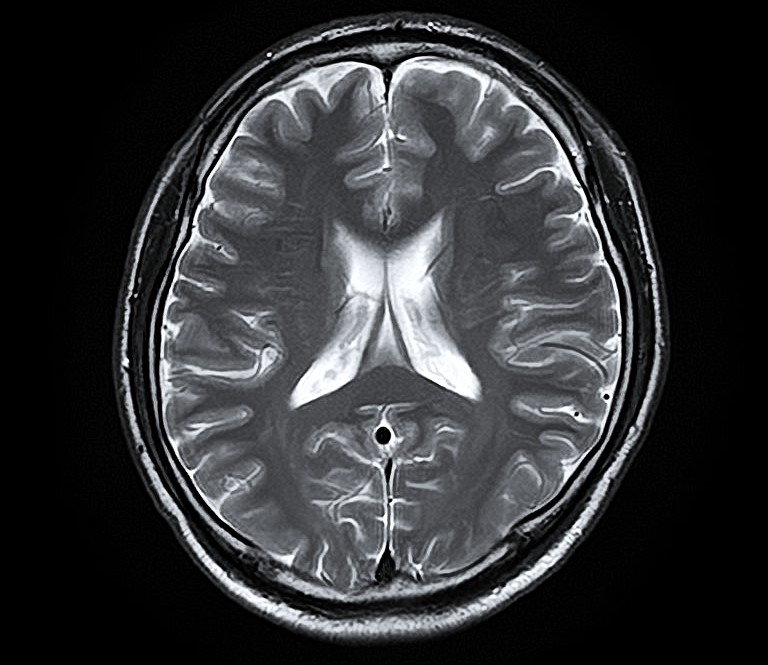

脳MRI・MRA検査

MRI(磁気共鳴画像)とMRA(磁気共鳴血管画像)を用いて、脳の断面や血管の状態を詳しく確認する検査です。

痛みや放射線被ばくの心配がなく、寝ているだけで脳の健康状態を調べることができます。

自覚症状のない小さな病変の早期発見を目指します。

脳MRI・MRA診断画像1

この検査でわかること

• 脳出血の原因となる血管の異常

• 脳腫瘍の有無

• 加齢や認知症に伴う脳の変化

• 自覚症状のない小さな脳梗塞の跡